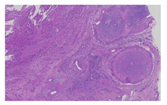

EGPA又称Churg-Strauss综合征,较为罕见,是一种富于嗜酸性粒细胞的坏死性肉芽肿性炎,常累及呼吸道,表现为哮喘和嗜酸性粒细胞增多症,约40%患者可累及消化道。主要累及小血管和毛细血管,偶尔也会累及中等动脉和静脉。典型的组织学表现是以血管为中心的大量嗜酸性粒细胞浸润(图1),血管周围形成肉芽肿,可伴血管中膜肉芽肿性纤维素样坏死[3]。肠壁结构可正常,可伴急性缺血、溃疡和穿孔[5]。